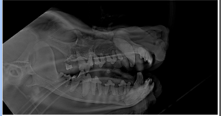

Clinical uses of Adaptix - Dentistry

Excellent definition of jaw and teeth

Patients can be put in 1 lateral recumbency and whole jaw x-rayed